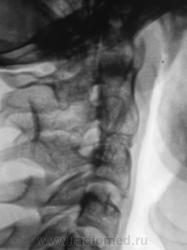

Подросток направлен в рентгеновский кабинет с диагнозом "сколиоз"...

Сколиоз-то сколиоз, но генеза "аномального".

Это синостоз тел верхних шейных позвонков и С6-С7? И боковые клиновидные полупозвонки в верхнегрудном отделе? Это синдром Клиппеля-Файля? А может и Шпренгеля...